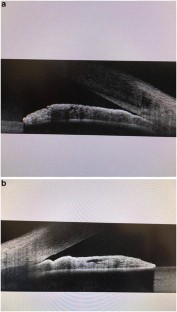

Fig. 1

Fig. 2